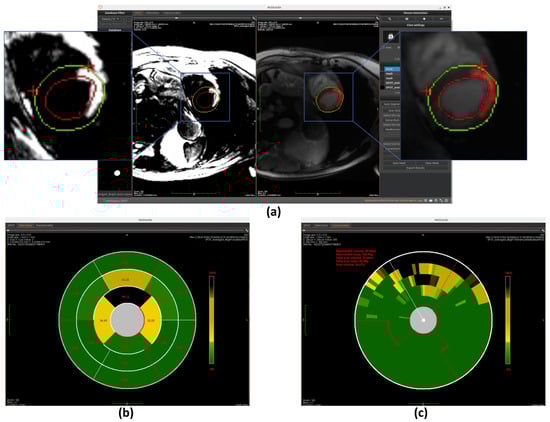

Our implementation first normalizes image intensities (0–255 range) before applying Otsu’s algorithm with three thresholds to classify pixels into distinct tissue categories (scar, gray zone, and healthy tissue). This provides an initial binary scar map that serves as input for subsequent refinement processes. The completely automated threshold selection requires no manual parameter adjustment, ensuring consistent performance across different cases (example of scar detection using Otsu is shown in Figure 7a).

Once the segments are accurately divided, the model calculates the scar area as a percentage of the total area within each segment. This is done by measuring the number of pixels corresponding to the scar in each segment and dividing it by the total number of pixels in that segment. These percentage values are then mapped to the corresponding positions on the bullseye plot, visually representing the spatial distribution of myocardial scars, as shown in Figure 7b, Figure 10b, and Figure 11b.

Once the segmentation is established, the model quantifies transmurality by assessing the proportion of scar tissue along each chord. For each chord, the ratio of scar thickness to the total myocardial wall thickness along the corresponding radial path is computed, reflecting the extent of myocardial wall affected. These transmurality values are then visualized in the bullseye plot, offering a high-resolution visualization of scar depth throughout the myocardium, as shown in Figure 7c, Figure 10c, and Figure 11c.

Figure 7. Overview of scar detection using the Otsu method. (a) Detected myocardial scar visualized on the BR-LGE image—highlighted as the red region between the left ventricular endocardium (red circle) and the epicardium (green circle), alongside comparison with the corresponding BL-LGE image. (b) Infarct size representation using an AHA 16-segment bullseye model. (c) Transmurality assessment using a bullseye plot with 100 equally spaced chords.